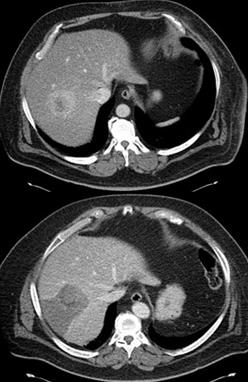

Radioembolization of liver tumors using Yttrium-90 products TheraSphere® and SIR-Spheres®

5.3 cm diameter hepatocellular carcinoma in segment 7 of the right hepatic lobe was treated twice with TheraSphere in a subsegmental fashion (“radiosegmentectomy”). The second CT was taken 8 months after the first radioembolization procedure. 12 months after the first radioembolization, his medical condition improved to allow a right hepatectomy. The pathologic specimen revealed no residual carcinoma in the resected liver.